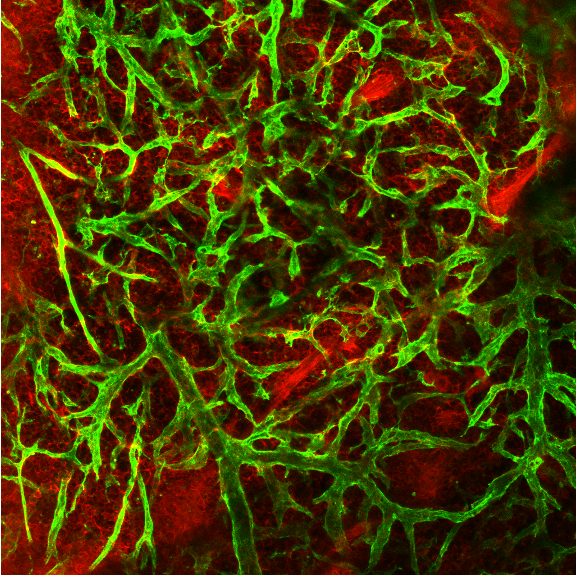

We systematically investigate the in vivo behavior and fate of drug delivery systems using advanced imaging and analytical tools, including intravital fluorescence microscopy, transmission electron microscopy, and synchrotron radiation-based imaging. Our studies focus on how delivery systems interact with physiological and immune barriers, such as the mononuclear phagocyte system (especially in the liver and spleen), vascular endothelium, and immune cell subsets. We analyze circulation kinetics, biodistribution profiles, cellular uptake mechanisms, and clearance pathways to elucidate the principles that govern delivery efficiency and target-site accumulation. These mechanistic insights guide the rational optimization of carrier design to improve therapeutic precision and minimize systemic toxicity.

2025[1] W. Jiang#, Z. Guo#, Q. Wang#,*, Z. Chen, W. Dong, Q. Liang, Y. Hao, H. Pan, C. Zeng, H. Liu* ,Y. C. Wang*. Enhanced nanoparticle delivery across vascular basement membranes of tumours using nitric oxide. Nature Biomedical Engineering. 2025, doi:10.103

2024[1] Q. Wang#, Q. R Liang#, J. X. Dou, H. Zhou, C. C. Zeng, H. M. Pan, Y. Q. Shen, Q. Li, Y. Liu, D. T. Leong*, W. Jiang*, Y. C. Wang*. Breaking through the basement membrane barrier to improve nanotherapeutic delivery to tumors. Nature Nanotechnology. 202